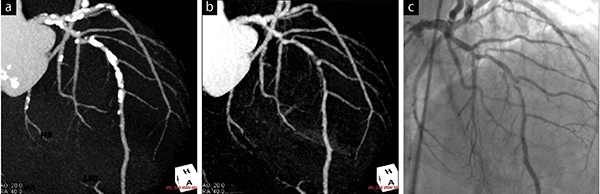

図1 サブトラクションcoronary CTAの1例

通常のcoronary CTA(a)では強い石灰化のため、左前下行枝の評価は難しい。サブトラクション処理(b)によって石灰化は除去され、カテーテルによる冠動脈造影(c)と同様の評価が可能であった。